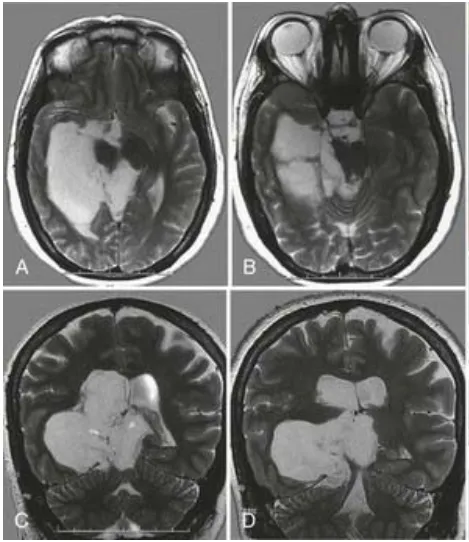

44岁女性莱娜,长期反复的癫痫发作已经让她苦不堪言,检查发现右侧脑室内见一巨大肿瘤正在扩散。 术前MRI 脑肿瘤相关性癫痫是癫痫的一个类型,通常由颅内肿瘤本身或其占位效应导致病灶...